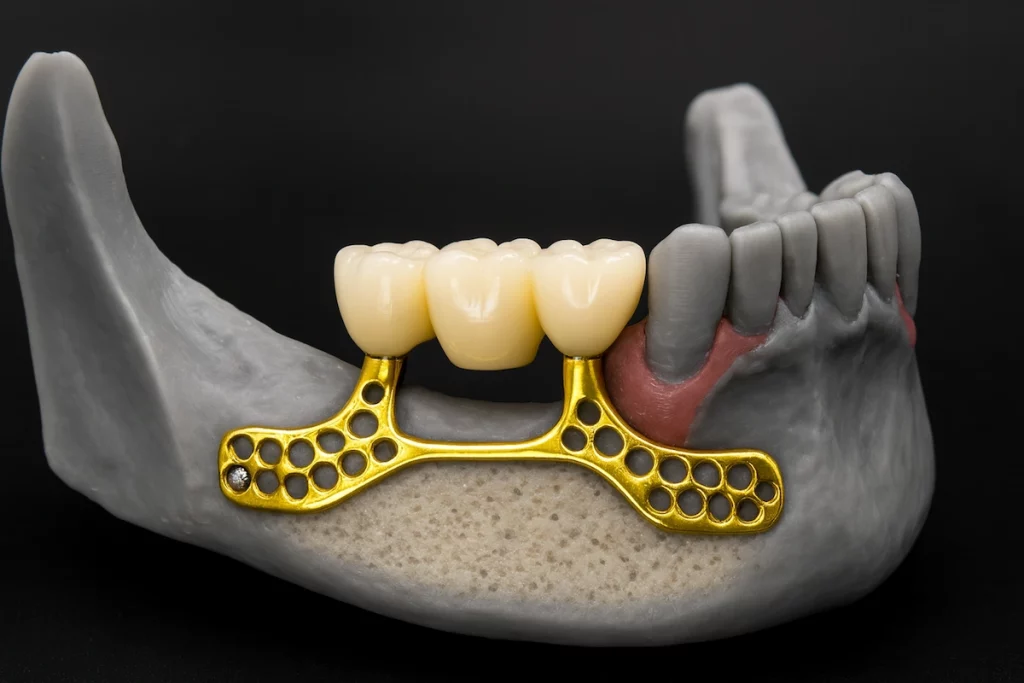

2. Subperiosteal Implants

Subperiosteal implants are the best alternative for patients lacking enough jawbone to ensure the solidity of endosteal. Subperiosteal implants are dug in the middle layer between the bone and the mucous membrane.